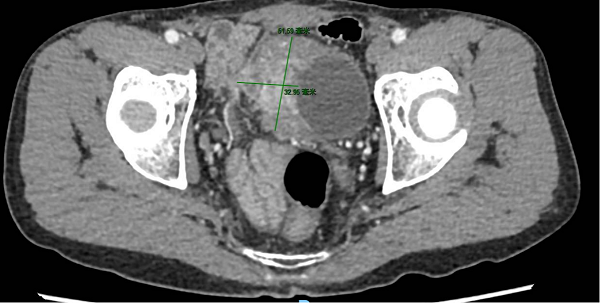

術(shù)前影像提示膀胱右側(cè)壁巨大腫瘤,侵犯腹膜及膀胱外脂肪組織